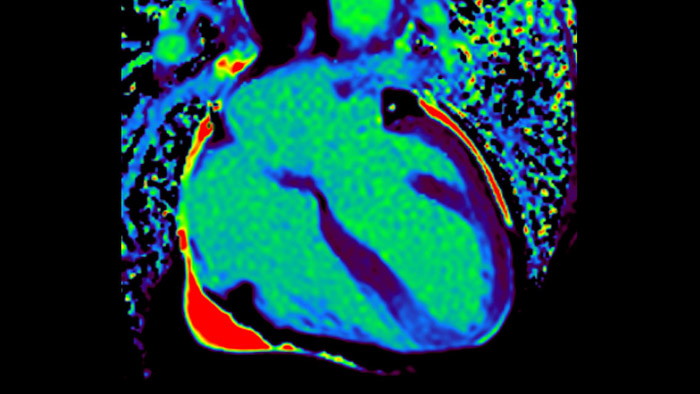

Today's diagnostics often cannot detect heart dysfunction until symptoms occur. MyoStrain utilises segmental strain to measure 48 segments of the heart and provides physicians with a unique diagnostic tool to help identify regional dysfunction before the heart as a whole is affected.

IntelliSpace Portal MR Caas5,6 Strain7 assists in patient diagnosis and monitoring by providing global strain parameters such as global longitudinal strain (GLS), global circumferential strain (GCS), and global radial strain (GRS), using short and long axis MR images, as well as describing the myocardium deformation- such as shortening, thickening, and lengthening during the cardiac cycle.

IntelliSpace Portal MR Caas5,6 4D Flow post-processing solution enables generation of 3D volume reconstructions, to visualise and evaluate blood flow in cardiovascular structures, including heart valves, chambers, and vessels, based on cardiovascular MR 4D Flow imaging.